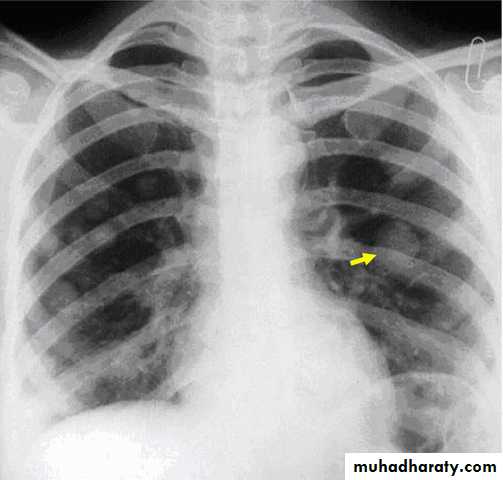

Chest x- ray to exclude metastasis

3. Chest x ray: If hCG titer plateau or rises.

k. embolization and respiratory symptoms.

Chest examination: finding if respiratory embolization.